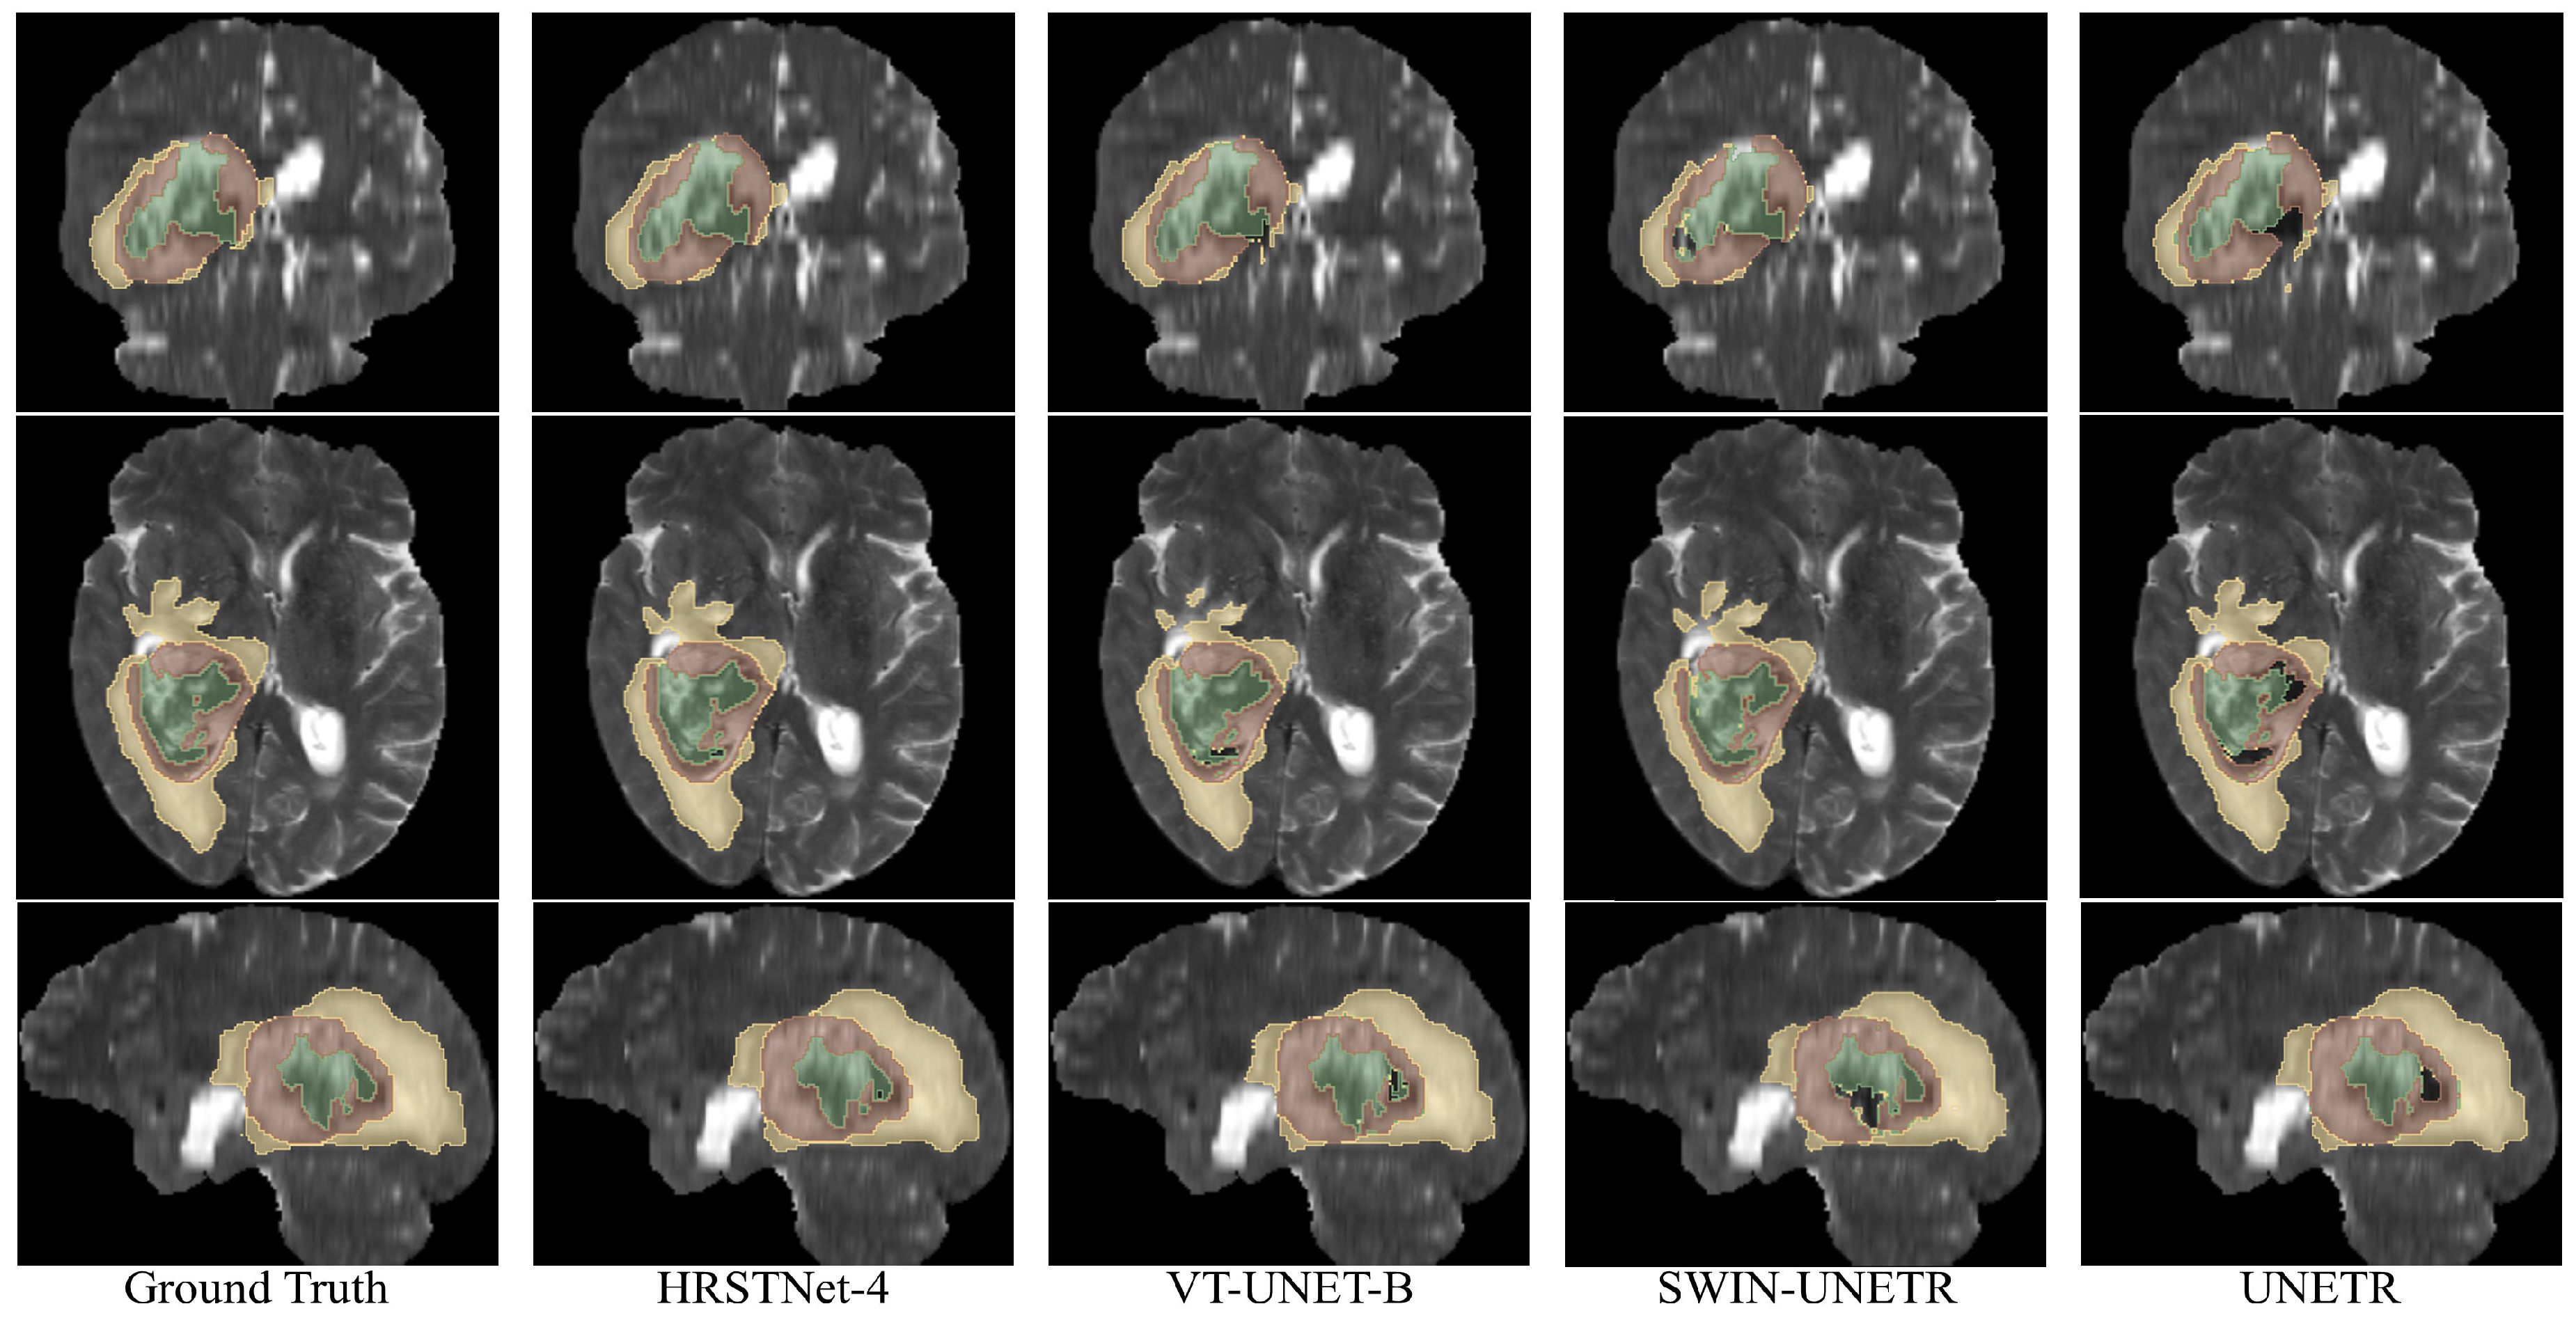

4.4. Experimental Results on BraTS 2021

| Optimized UNet [34] | 1345.57 | 51.23 | 10.62 | 87.84 | 5.66 | 92.21 | 17.18 | 83.67 | 9.04 | 87.65 |

| Extending nnUNet [35] | 1657.97 | 87.41 | 2.99 | 92.69 | 3.62 | 93.40 | 2.50 | 90.79 | 2.86 | 93.89 |

| UNETR [8] | 175.85 | 102.45 | 11.04 | 86.18 | 6.18 | 91.40 | 18.31 | 81.80 | 8.63 | 85.33 |

| Swin UNETR [10] | 1218.79 🟉 | 240.96 | 9.84 | 86.13 | 6.06 | 90.42 | 15.27 | 83.36 | 8.19 | 84.62 |

| VT-UNet-B [9] | 124.03 | 20.76 | 13.36 | 87.31 | 8.96 | 91.20 | 18.69 | 83.85 | 12.44 | 86.87 |

| HRSTNet-2 | 107.47 | 7.19 | 8.99 | 87.22 | 4.15 | 92.06 | 15.63 | 82.64 | 7.20 | 86.95 |

| HRSTNet-3 | 202.76 | 50.07 | 8.06 | 86.94 | 4.79 | 91.81 | 13.91 | 82.20 | 5.50 | 86.80 |

| HRSTNet-4 | 318.43 | 266.33 | 8.94 | 87.48 | 4.09 | 91.90 | 15.62 | 82.92 | 7.11 | 87.62 |